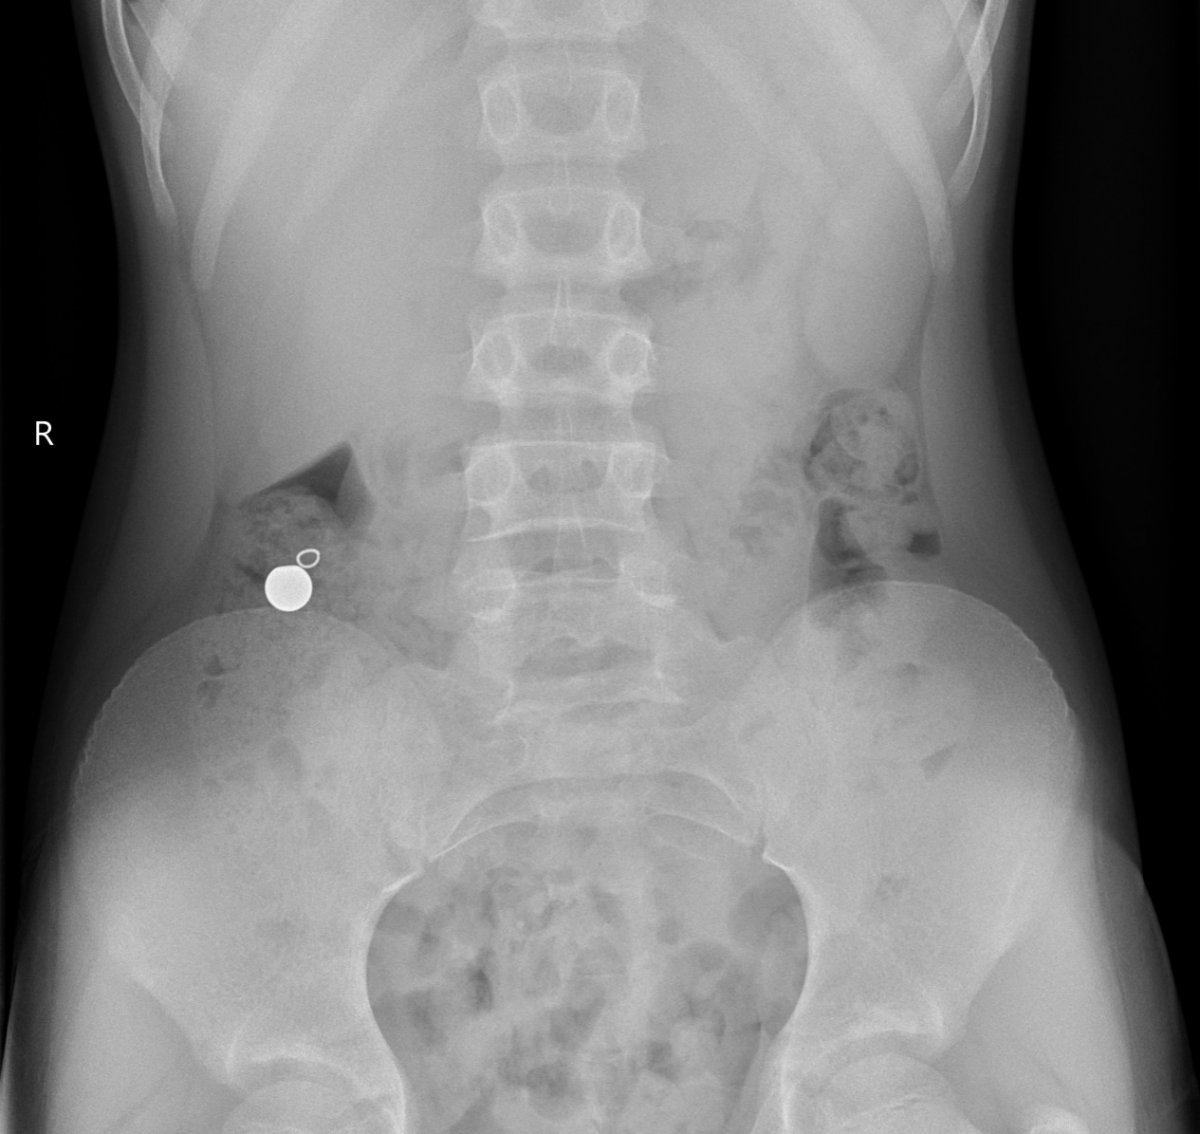

Galéria k článku Rodičia, POZOR! Šíri sa NEBEZPEČNÝ TikTok trend: Viacero detí skončilo v nemocnici

Zdroj: FN Motol